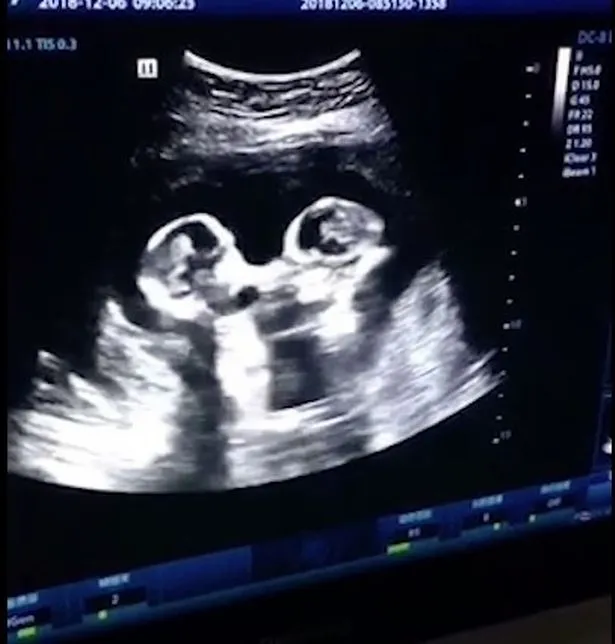

Szívinfarktus kerülgette az első gyermekét váró, 16 éves Sophie Scottot, amikor az orvos kezébe adta a kisbabájáról készült első ultrahangfelvételt.

A növekvő kis magzat mögött ugyanis egy rémisztő arc tűnt fel, ami leginkább egy eltévedt alienhez hasonlított – számolt be róla a Mirror.

Az ijesztő lényt először a kismama kedvese, a 24 éves Stephen vette észre, Sophie boldogsága pedig egyből rémületbe csapott át.

„A kislányunk mögött feltűnt egy másik szempár is. A szempárhoz tartozó arc pedig nagyon amorf volt, mintha egy földönkívüli lett volna”